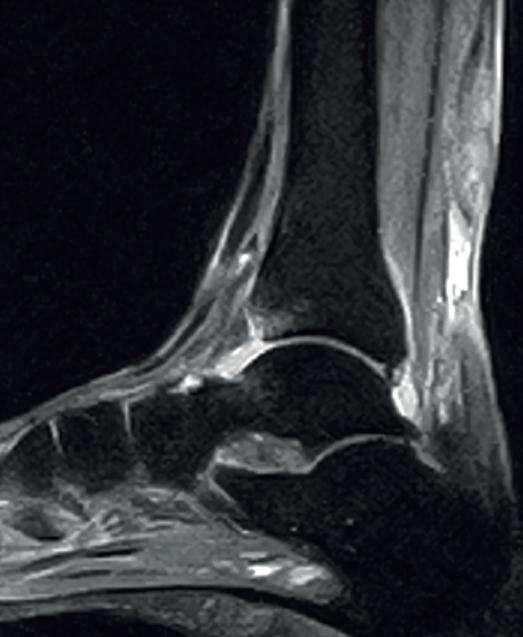

Figure 4. Sagittal magnetic resonance imaging view showing subacute non-insertional Achilles tendon rupture. Hyperintensity area between the two extremities.

Lastly, in acute Achilles tendon rupture, MRI shows the hematoma and also herniation of Kager's fat pad - these signs being similar to those identified by ultrasound (Figure 4). In chronic ruptures, MRI is the best diagnostic tool. Loss of continuity between the extremities is observed in T1 sequencing, while T2 imaging evidences hyperintensity between the two tendinous extremities due to the interpositioning of connective tissue and cicatricial changes(36).